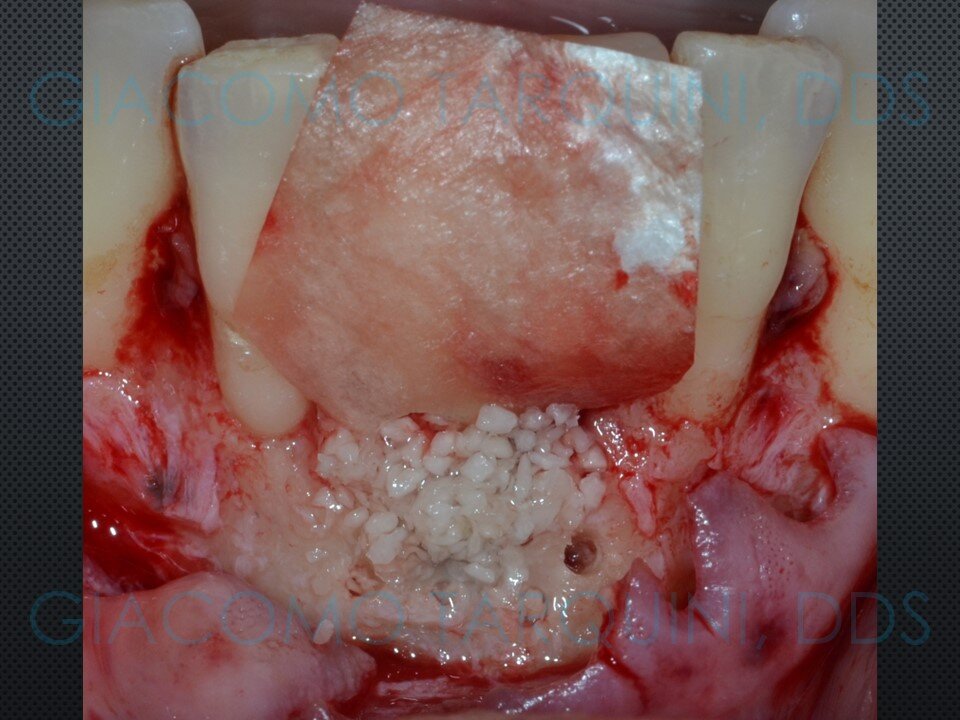

Viene presentato un caso di rigenerazione ossea guidata attorno a un impianto che aveva perso parte del suo supporto osseo a causa di una pregressa peri-implantite. Le spire esposte vengono decontaminate sfruttando le note proprietà della cavitazione ultrasonica per mezzo del dispositivo “Piezoclean by Dr. Giacomo Tarquini”, mentre la fase rigenerativa viene effettuata secondo il protocollo denominato “Poncho technique”. Questo approccio consente una ricostruzione prevedibile del tessuto osseo senza dover necessariamente rimuovere l'abutment e la protesi al fine di ottenere una guarigione sommersa.

- Eseguire il protocollo rigenerativo di scelta (ad es. mediante membrane di tipo riassorbibile o non riassorbibile)

CASO CLINICO: